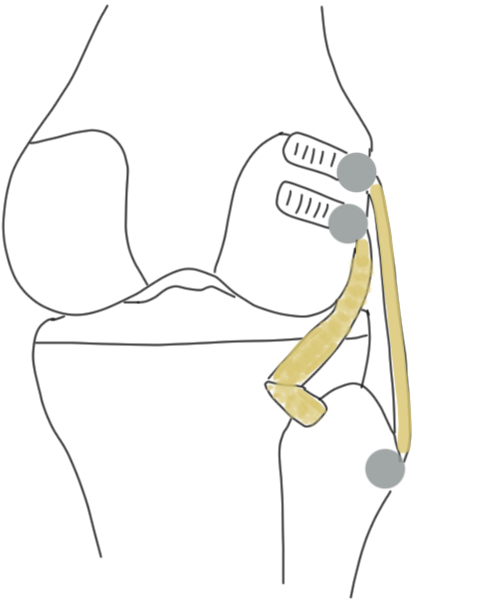

C. Arciero reconstruction (single graft reconstruction of LCL and Popliteus)

Concept

- drill LCL and popliteus tunnels as per LaPrade

- single tunnel in fibular

- reconstruction popliteus and LCL with single graft